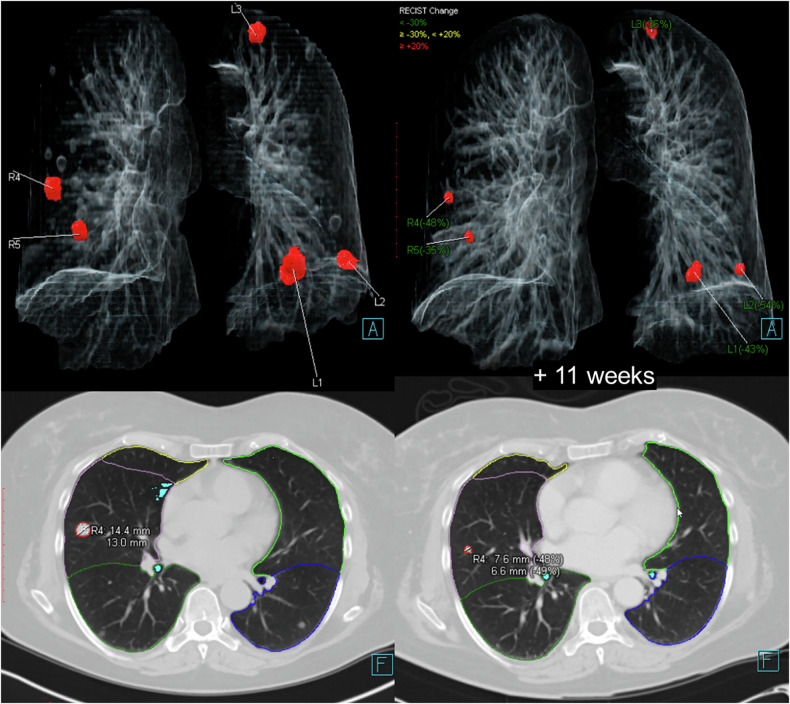

Methods: In this single-center study, patients with nodules and ≤ 2 chest computed tomography (CT) examinations were retrospectively selected. An AI-based algorithm was used for automated nodule detection and matching. The matching rate and the causes for incorrect matching were evaluated for the ten largest lesions (5-30 mm in diameter) registered on baseline CT. The dependence of the matching rate on nodule number and localization was also analyzed.

Results: One hundred patients (46 females), with a median age of 62 years (interquartile range 57-69), and 253 CTs were included. Focusing on the ten largest lesions, 1,141 lesions were identified, of which 36 (3.2%) were other structures incorrectly identified as nodules (false-positives). Of the 1,105 identified nodules, 964 (87.2%) were correctly detected and matched. The matching rate for nodules registered in both baseline and follow-up scans was 97.8%. The matching rate per case ranged 80.0-100.0% (median 90.0%). Correct matching rate decreased in follow-up examinations to over 50 nodules (p = 0.003), with an overrepresentation of missed matching. Matching rates were higher in parenchymal (91.8%), peripheral (84.4%), and juxtavascular (82.4%) nodules than in juxtaphrenic nodules (71.1%) (p < 0.001). Missed matching was overrepresented in juxtavascular, and incorrect assignment in juxtaphrenic nodules.

Conclusion: The correct automated-matching rate of metastatic pulmonary nodules in follow-up examinations was high, but it depends on localization and a number of nodules.

Relevance statement: The algorithm enables precise follow-up matching of pulmonary nodules, potentially providing a solid basis for standardized and accurate evaluations. Understanding the algorithm's strengths and weaknesses based on nodule localization and number enhances the interpretation of AI-based results.

Key points: The AI algorithm achieved a correct nodule matching rate of 87.2% and up to 97.8% when considering nodules detected in both baseline and follow-up scans. Matching accuracy depended on nodule number and localization. This algorithm has the potential to support response evaluation criteria in solid tumor-based evaluations in clinical practice.